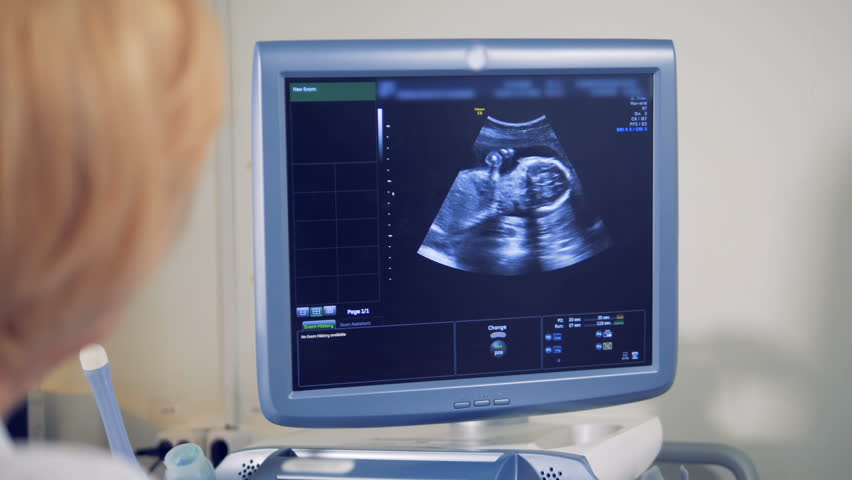

A dating scan is an ultrasound scan carried out at around 12 weeks of pregnancy, that's used to work out your due date . It's likely to be the first time you see your baby and hear their heartbeat . This scan is also used to check that your baby's development is on track and is often part of combined screening for genetic variations, such as Down's syndrome , Edwards' Syndrome and Patau's Syndrome .

What happens at a dating scan ? The dating scan usually takes about 30 minutes (NHS 2015a, Healthlink BC 2019, SOGC 2019) . Nearly all ultrasounds after 10 weeks can be done through your tummy (Butt and Lim 2014) . Most hospitals or ultrasound clinics ask you to arrive with a full bladder .

The 10-week ultrasound scan is also called a dating scan , as it is used to determine the gestational age of the baby and predict the due date . The nuchal translucency test is part of this scan . Some parents may choose to get a printed picture of the scan to preserve as a memento .